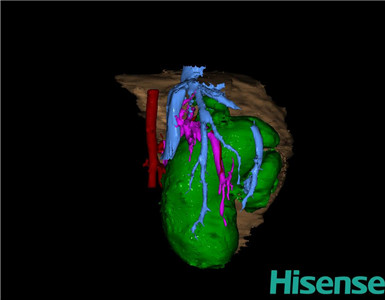

CT结果输入海信CAS系统后行3D重建及手术规划后,于2015-3-24全麻下行“胆总管囊肿切除+胆囊切除+胆总管-空肠吻合术”手术治疗:

术前三维重建及手术方案设计:

将0.625mm双源薄层CT资料的静脉期和动脉期Dicom格式文件导入海信CAS系统。

通过调节窗宽窗位调整CT序号,对肝实质,胆囊,下腔静脉,肿瘤,肝动脉、门静脉及肝静脉等进行三维重建;系统自动计算肝脏体积。

术前手术方案的规划。

术前三维重建:

重建图片